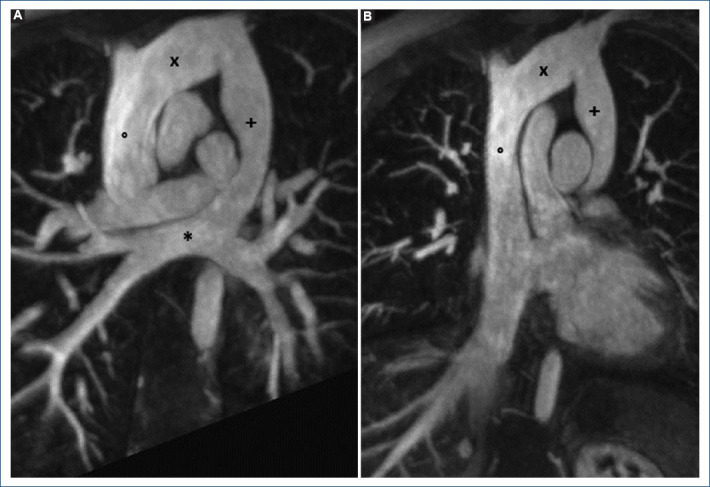

[Anomalous connection of supracardiac pulmonary veins: the value of cardiac magnetic resonance imaging and the use of 4D flow in its evaluation].